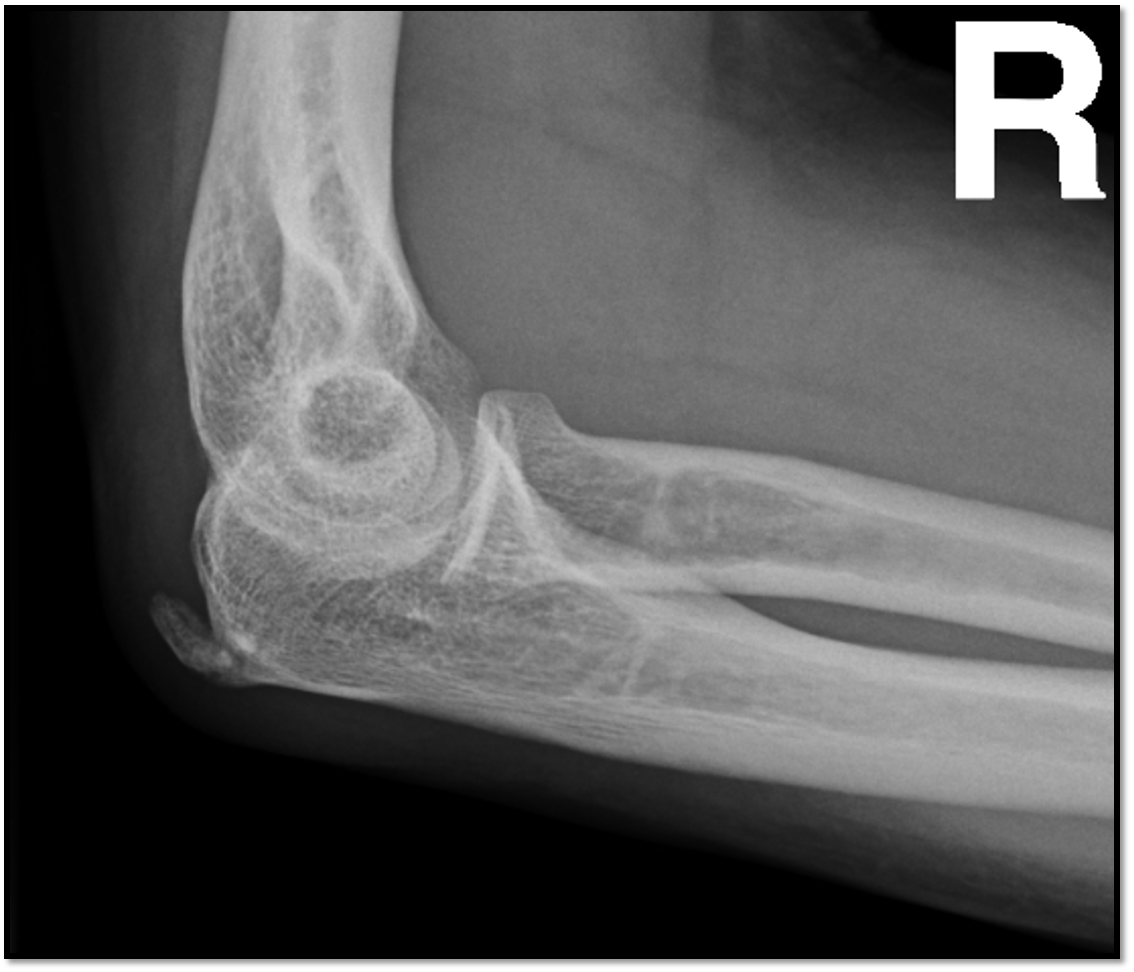

Q

What is the positioning fault?

How would you fix it?

A

• hand is too low

• lateral condyle more distal

• need to raise hand